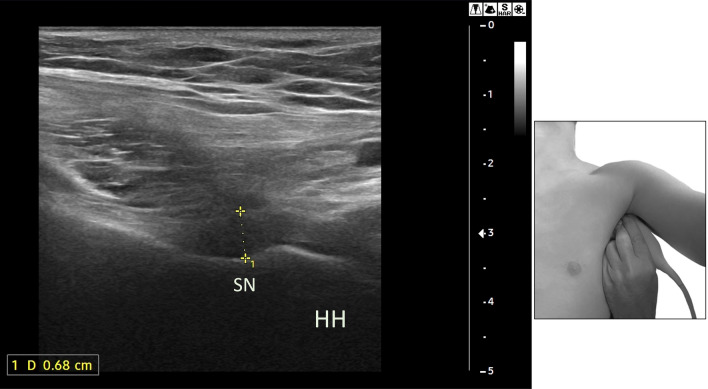

Rotator interval region, long head of biceps tendon (LHBT), axillary pouch (AP), and posterior joint capsule (PJC)

The RI region is superiorly and laterally delimitated by the inferior margin of the supraspinatus (SST) tendon, inferiorly and medially by the upper margin of the subscapularis (SUBT) tendon, medially by the coracoid process, laterally by the intersection of the coracohumeral (CHL) and superior glenohumeral ligament (SGHL) at LHBT, that contribute to form its pulley and prevent it from sliding medially. The coracohumeral ligament (CHL) originates from the coracoid process and goes laterally inserting into the greater humeral tubercle and to the lesser one, enveloping LHBT and helping to form its pulley (along with SST and SUBT tendon aponeurosis) (Fig. 1). Moreover, CHL goes to the anterior margin of SST tendon forming the lateral pulley complex. This part is recalled as the anterior pillar of the rotator cable which represents the most important anchorage and stress dispersion system for the SST tendon at the humeral head [11, 12]. The tension of CHL is an important determinant of shoulder mobility, particularly in external rotation and abduction. The humeral greater tuberosity and the lesser tuberosity are bone protrusions delimiting the bicipital groove. However, the groove extends cranially to the protrusions, just below the surgical neck, where the LHBT leaves an impression on the bone (Fig. 2). The proximal part of the bicipital groove is normally visible at US investigation; the CHL inserts on the upper edge of the great tuberosity, on its prominence (transversely) and on the superior crest of the lesser tuberosity, as described in the classical anatomical literature. Thus, CHL and LHBT are strictly paired when investigated by the US, displaying a specific pattern. Finally, the AP represents the inferior part of the glenohumeral capsule (Fig. 3), and it’s placed between the anterior and posterior bands of the inferior glenohumeral ligament (IGHL) [4]. Usually, the AP displays a thin wall thickness, generally not higher than 3 mm [13]. The PJC is located below the infraspinatus tendon (IST) and expands during the external rotation of the arm when the joint effusion is present; conversely, in the case of AC, it contracts.

Fig. 1.

Right humerus. GT great tuberosity; LT lesser tuberosity; CHL coracohumeral ligament; SGHL superior glenohumeral ligament; LHBT long head biceps tendon; SN surgical neck. In the small box, pulley axial section of RI. SST supraspinatus tendon; SUBT subscapularis tendon; BT biceps tendon

Fig. 2.

Left humeral head: the bicipital groove (white arrows and dashed white line) begins just below the surgical neck (SN, green arrows)